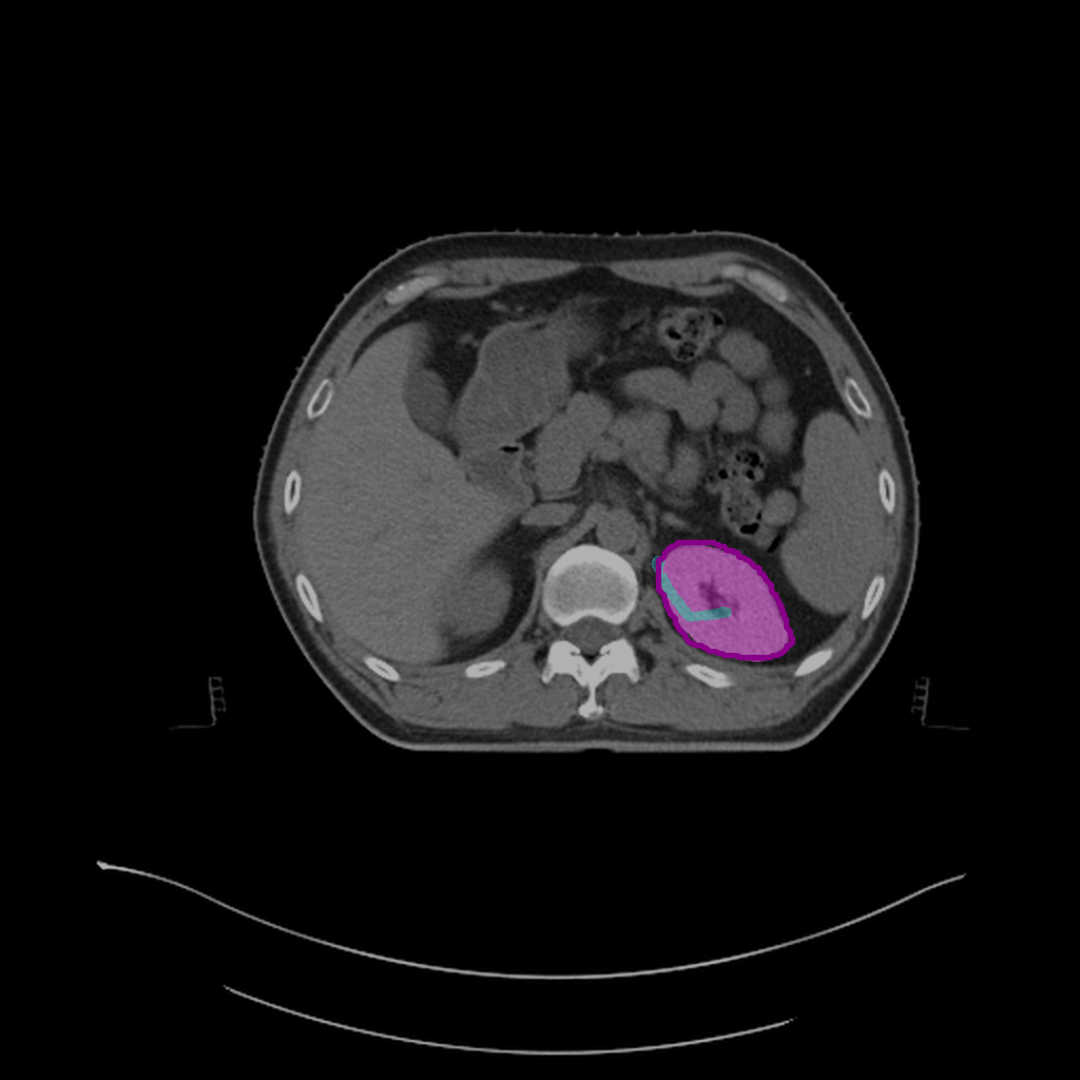

Refer to caption

(e) Mask after half correction.

(f) Mask after full correction.

Figure 4: Steps to correct segmentation masks for various abdominal organs, such as the spleen, left kidney, and liver, on different CT slices. Each subfigure shows the outline of reference segmentation contours, the predicted segmentation mask, and gaze points (blue) used for predictions based on gaze.